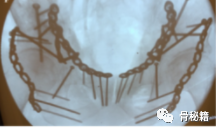

术中透视

通过正位,入口,出口位进行监控

术后检验,当然是CT扫描啦,就看你的自信程度了